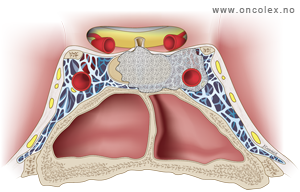

Knosp klassifikasjon brukes for å beskrive svulstenes utbredelse fra midtlinjen og ut til sidene. Klassifikasjonen deler svulstene inn i grad fra 0 til 4, hvor grad 0 er svulster i hypofysegropen uten utbredelse inn i sinus cavernosus, og grad 4 er svulster som omslutter den indre halsarterien (arteria carotis interna). Grad 4 svulster og svulster som brer seg ut til siden for den indre halsarterien (Knosp grad 3) er svært vanskelig å fjerne fullstendig med operasjon.

Bildeserie av stadieinndeling av hypofysesvulster (Knosp klassifikasjon)